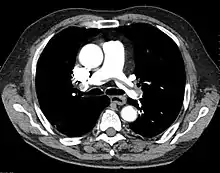

"Saddle" embolism on CT. The filling defect in the pulmonary artery is the clot.

A pulmonary embolism (PE) is an obstruction of the pulmonary arteries.[13] Deaths from PE have been estimated at ~100,000 per year in the United States. However, this may be higher in recent years.[16] Most often, the obstruction is a blood clot that traveled from elsewhere in the body. Most commonly, this is from a deep vein thrombosis (DVT) in the legs or pelvis.[13] Risk factors are conditions that increase the risk of clotting. This includes genetic (factor V Leiden) and acquired conditions (cancer).[17] Trauma, surgery, and prolonged bed-rest are common risks. Covid-19 is a recent risk factor.[18]

This obstruction increases the pulmonary vascular resistance. If large enough, the clot increases the load on the right side of the heart. The right ventricle must work harder to pump blood to the lungs. With back-up of blood, the right ventricle can begin to dilate. Right heart failure can ensue, leading to shock and death.[18]

A PE is considered "massive" when it causes hypotension or shock. A submassive PE causes right heart dysfunction without hypotension.[18]

A chest X-ray can rapidly identify a pneumothorax, seen as absence of lung markings. Ultrasound can show the lack of lung sliding. However, imaging should not delay treatment.[8] CT angiography is the standard of diagnosis of pulmonary embolism. Clots appear in the vasculature as filling defects.[18]